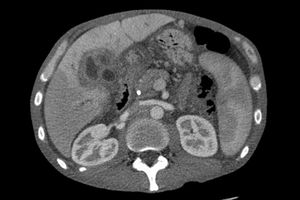

كثيرا ما يستخدم الكشف بالموجات فوق الصوتية على الكبد والقنوات المرارية كطريقة أولية لإجراء التصوير الباطني للمرضى الذين يشتبه في إصابتهم باليرقان (نتج عنه انسداد بقنوات الصفراء)[41] · [42] . ويمكن لهذا النوع من التصوير تحديد وجود انسداد و / أو تمدد بالمرارة ، الأمر الذي قد يكون- في بعض الحالات- كافيا لتشخيص سرطان قنوات الصفراء [43]. كما أن الأشعة المقطعية قد تساعد كذلك في توفير معلومات تشخيصية عن هذا النوع من السرطانات [44] · [45] · [46].وتعتبر درجة دقة التشخيص بالأشعة المقطعية كافية، و لكنها ربما تؤدي إلي عدم تقدير حقيقي لمدى انتشار الورم في القنوات المرارية[47].